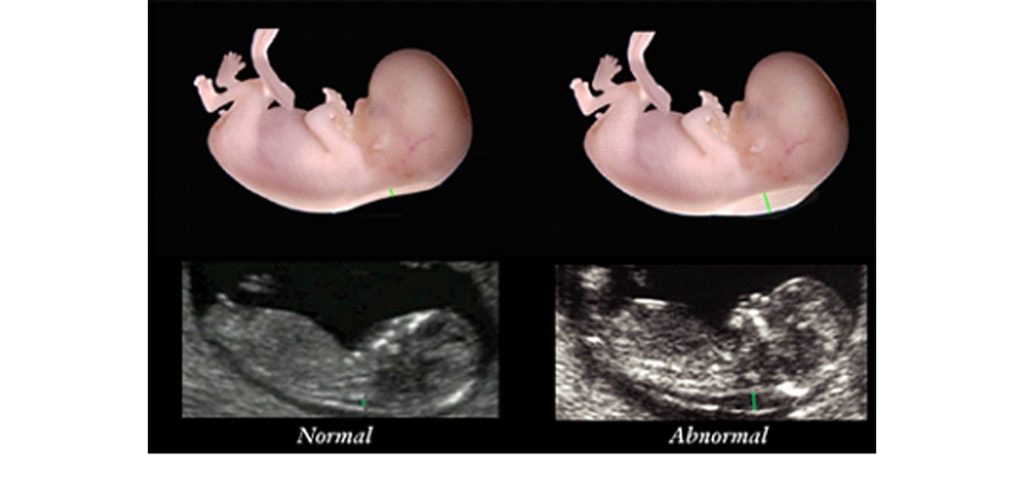

پہلے تین ماہ میں بچے کے اعضاء بن رہے ہوتے ہیں لہٰذا عموماً یہ مسائل اسی دوران پیش آتے ہیں تاہم یہ اگلی سہ ماہیوں میں بھی ہو سکتے ہیں۔ شفا انٹرنیشنل ہسپتال کی ماہر امراض نسواں ڈاکٹر ہما تسلیم کہتی ہیں کہ جینیاتی نقائص کی تشخیص کے لیے حمل کے 8 سے 10 ہفتوں میں سی وی ایس (chronic villus sampling) کی جاتی ہے۔ اس میں ماں اور بچے کے درمیان بننے والی نالی سے خلیے لے کر جائزہ لیا جاتا ہے۔

پھر 11 سے 13 ہفتوں کے دوران ایک سکین ہوتا ہےجسے این ٹی (nuchal translucency) کہتے ہیں۔ اس میں جنین کی گردن کی جلد کے نیچے پائے جانے والے مواد کا جائزہ لیا جاتا ہے۔ یہ معمول سے زیادہ ہو تو بچہ ڈاؤن سینڈروم اور امراض قلب کا شکار ہو سکتا ہے۔

اسی طرح حرام مغز کے مسائل (مثلاً کمر میں پھوڑے)، بچے کا سر معمول سے چھوٹا یا بڑا ہونا یا اس کے اندر پانی جمع ہونا جیسے مسائل کی تشخیص الٹرا ساؤنڈ سے ہو جاتی ہے۔ بچے میں امراض قلب کی تشخیص ہو تو زچگی ایسے ہسپتال میں ہونی چاہیے جہاں بچوں کا کارڈیئک سرجن موجود ہو۔ اس کے علاوہ خون کے ٹیسٹوں سے انفیکشن کا پتا لگایا جا سکتا ہے۔